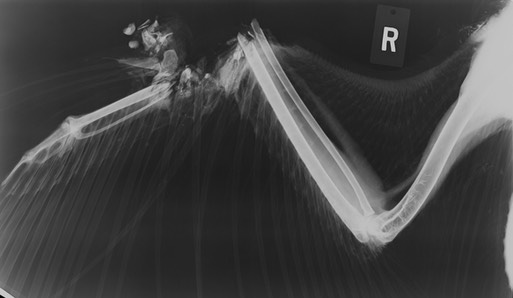

Bald Eagle 20-004

The eagle’s right wrist was completely shattered. There were also lead fragments in his stomach. We may have been able to successfully treat the lead poisoning, but the wing was not salvageable and the eagle was euthanized.